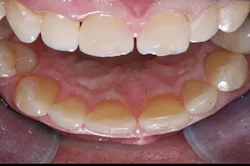

Intact lingual surfaces-If the lingual surfaces are worn through to dentin or carious, veneers are not indicated, and crowns should be placed. Lingual surfaces should be intact for veneers (figures 1, 2).

Figure 1: Two central incisors to be restored show deep facial restorations extending onto the lingual surfaces with a diastema present. These teeth would probably be better treated with crowns.